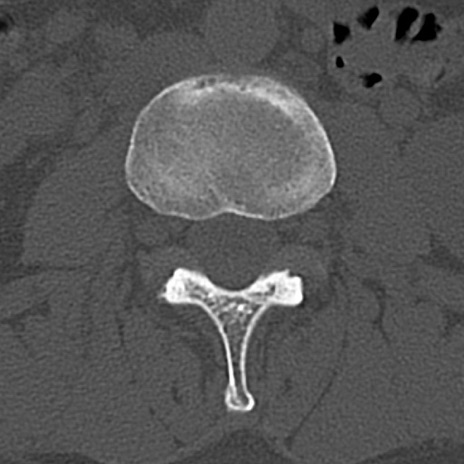

腰椎CT

横断像と矢状断像